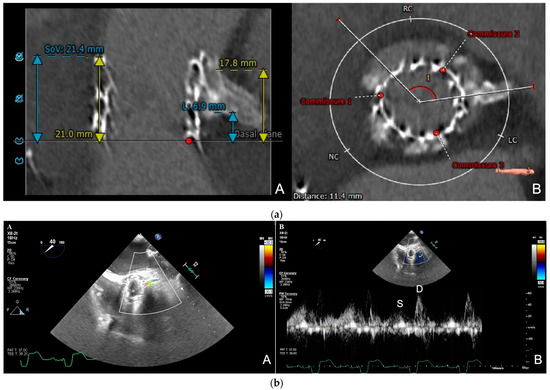

- Dvir, D.; Leipsic, J.; Blanke, P.; Ribeiro, H.B.; Kornowski, R.; Pichard, A.; Rodés-Cabau, J.; Wood, D.A.; Stub, D.; Ben-Dor, I.; et al. Coronary obstruction in transcatheter aortic valve-in-valve implantation: Preprocedural evaluation, device selection, protection, and treatment. Circ. Cardiovasc. Interv. 2015, 8, e002079. [Google Scholar] [CrossRef]

- Nomura, T.; Teruo, I.; Miyasaka, M.; Hirose, S.; Enta, Y.; Ishii, K.; Nakashima, M.; Saigan, M.; Toki, Y.; Sakurai, M.; et al. Detection of left coronary ostial obstruction during transcatheter aortic valve replacement by coronary flow velocity measurement in the left main trunk by intraoperative transesophageal echocardiography. J. Cardiol. 2023, 81, 97–104. [Google Scholar] [CrossRef]